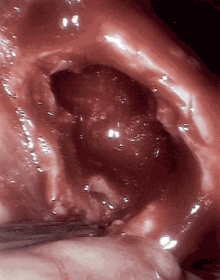

An open cavitation.

Cavitation, in biology, is the formation of cavities in an organ, especially in lung tissue as a result of tuberculosis. It can also be caused by squamous cell lung carcinoma after necrosis of the central part.[1]